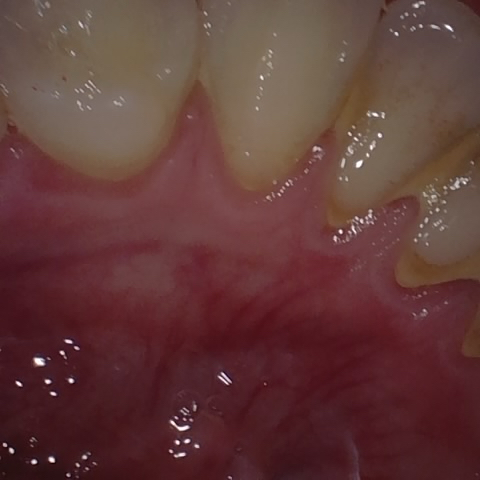

Annotated as "Good"